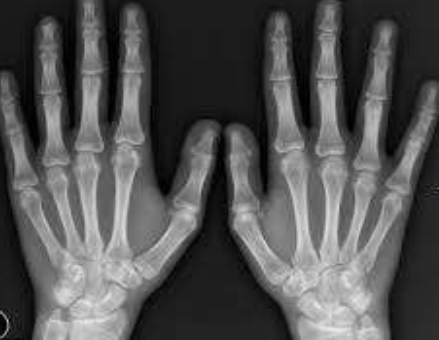

전리방사선 및 비전리방사선의 취급과 방사성동위원소를 이용한 행의학검사와 초음파검사 등 관리 및 취급 업무를 하는 사람을 말합니다. 보통 병원에 가서 엑스레이 검사를 하거나, CT, MRI 검사를 하는 사람들이 방사선사이고, 핵의학과, 방사선종양학과에서 일하는 사람도 방사선사입니다.